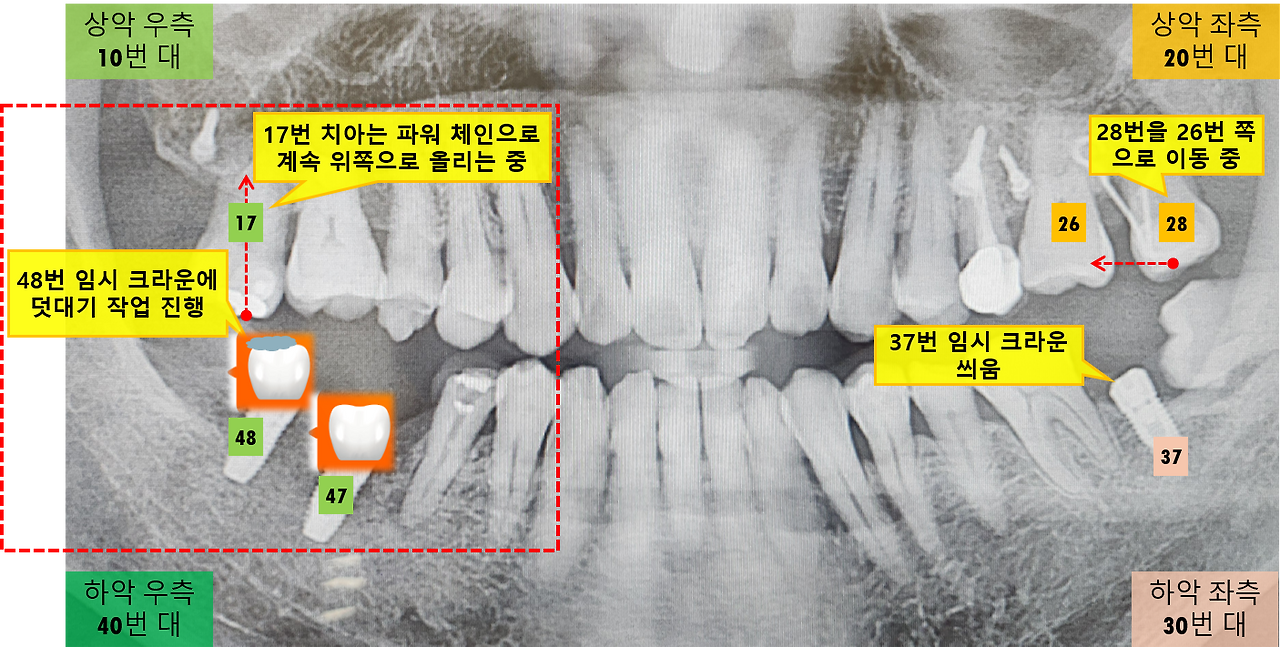

임시 크라운 덧붙이기(높이 조절) 작업(2026. 3. 16)

우측 상악 17번 치아를 위로 올리는 교정 작업은 꾸준히 진행이 되고 있습니다. 치아가 제자리를 잡으려면 '파워 체인'의 당기는 힘도 필요하지만, 아래쪽 48번 치아와의 맞물림(교합) 상태가 무엇보다 중요합니다.

17번과 48번 치아의 교합 상태를 확인해 보니 간극이 있어, 씹는 기능은 물론 17번 치아를 올리는 힘이 부족하다고 합니다. 그래서 17번 치아의 파워 체인을 더 강한 것으로 교체하고, 48번 임시 크라운 위에 레진을 덧대어 높이를 높이는 치료가 진행되었습니다.

여러 번의 교합 상태 확인을 통해 굳은 레진을 다듬어 교합을 맞춘 후, 표면을 매끄럽게 연마하고 잇몸에 붙은 레진까지 모두 제거하며 오늘의 진료가 마무리되었습니다. 이제 오른쪽 17번과 48번 치아가 이전보다 더 잘 교합이 될 것이고, 이를 통해 17번 치아가 빠르게 위로 올라가서 제자리를 잡을 것입니다. 이런 단계를 거쳐서 17번 치아가 완전히 자리를 잡게 되면 최종 보철물로 교체하게 될 것이네요.